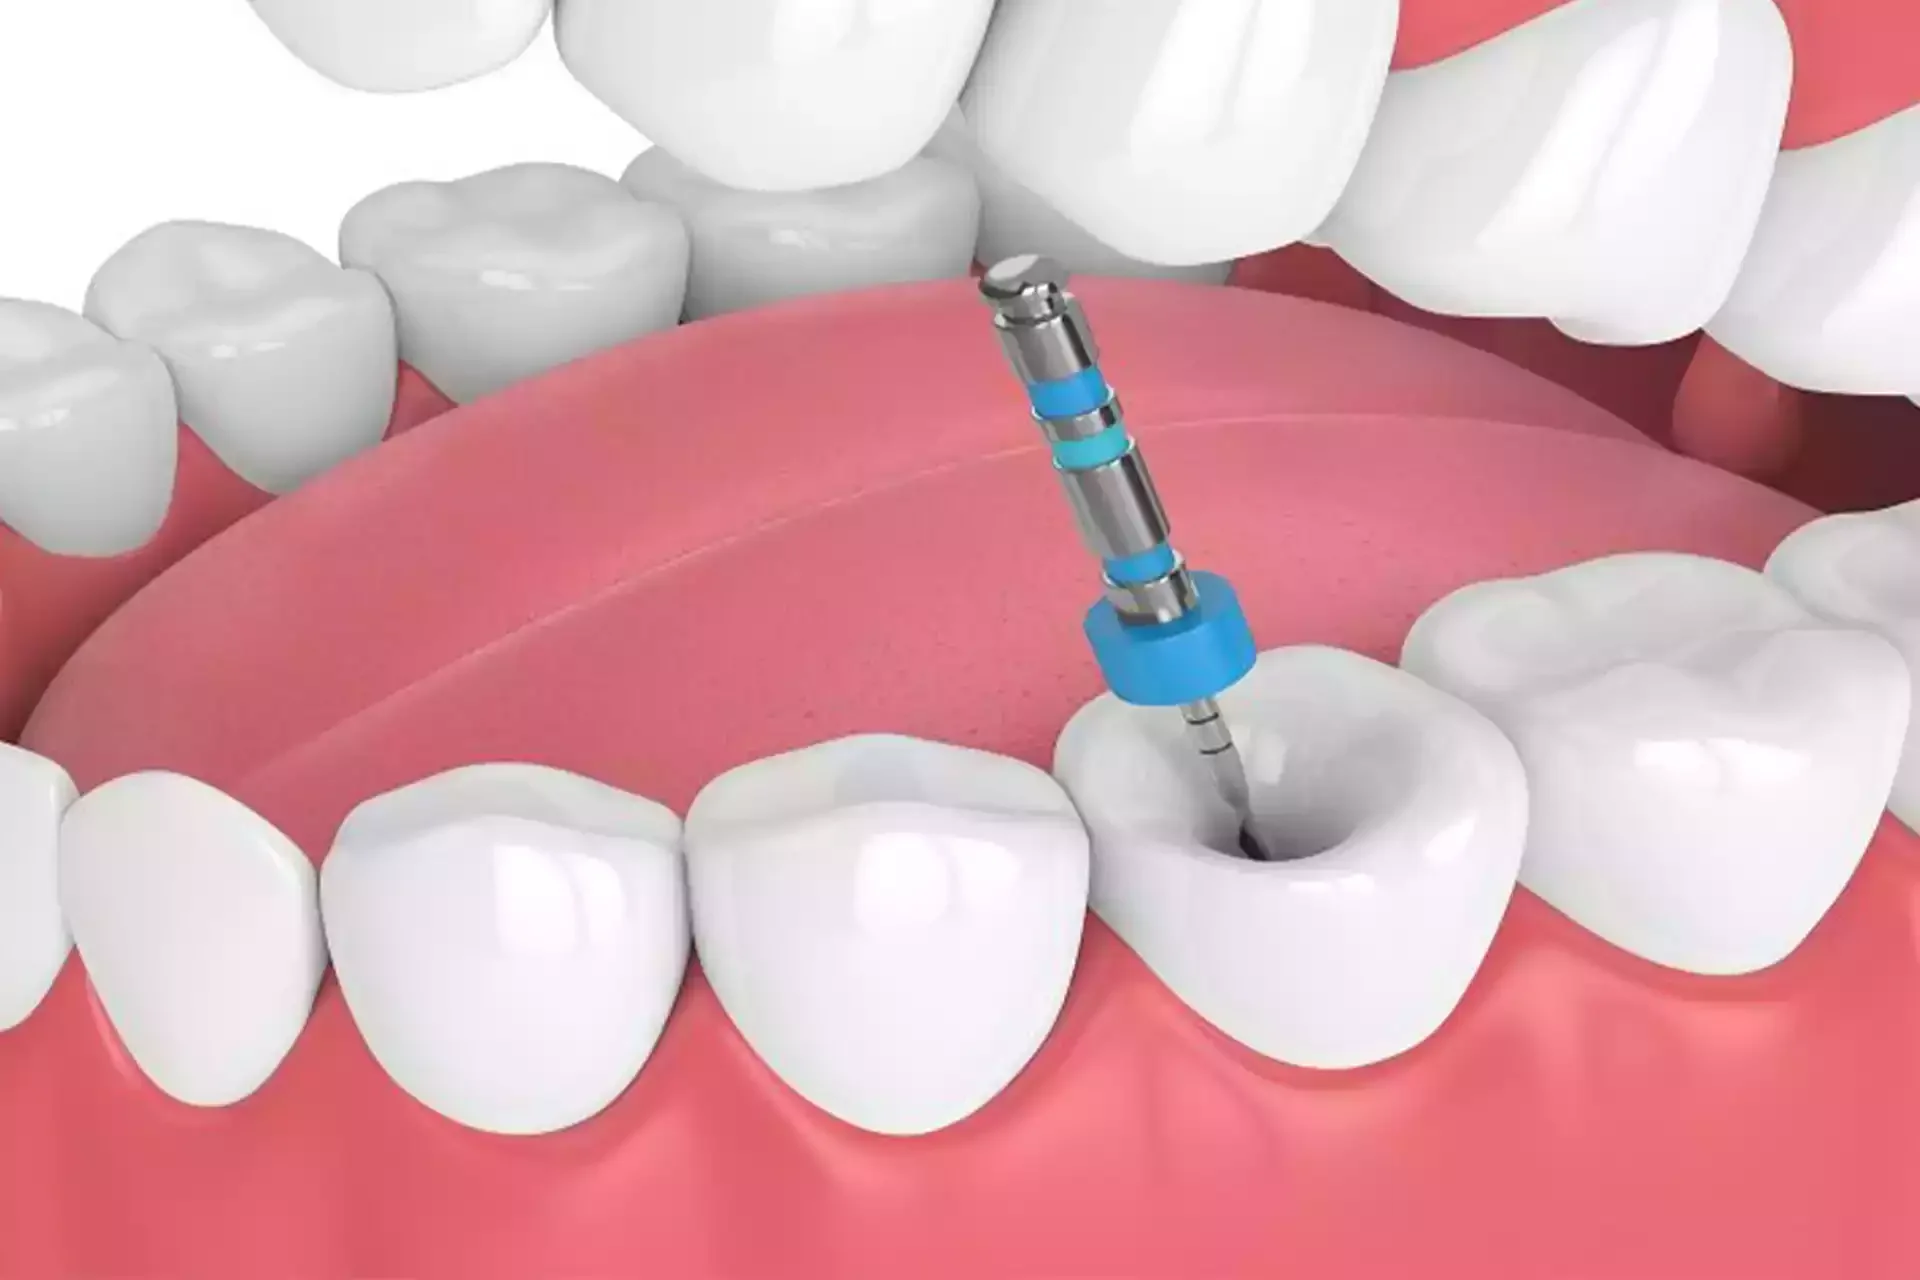

Endodoncia

La endodoncia es un tratamiento que elimina la infección del interior del diente para conservarlo y aliviar el dolor, evitando su extracción y devolviendo su función.

Retratamiento de Endodoncia

El retratamiento de endodoncia se realiza cuando un tratamiento previo no ha sanado correctamente, permitiendo limpiar nuevamente el conducto y salvar el diente.